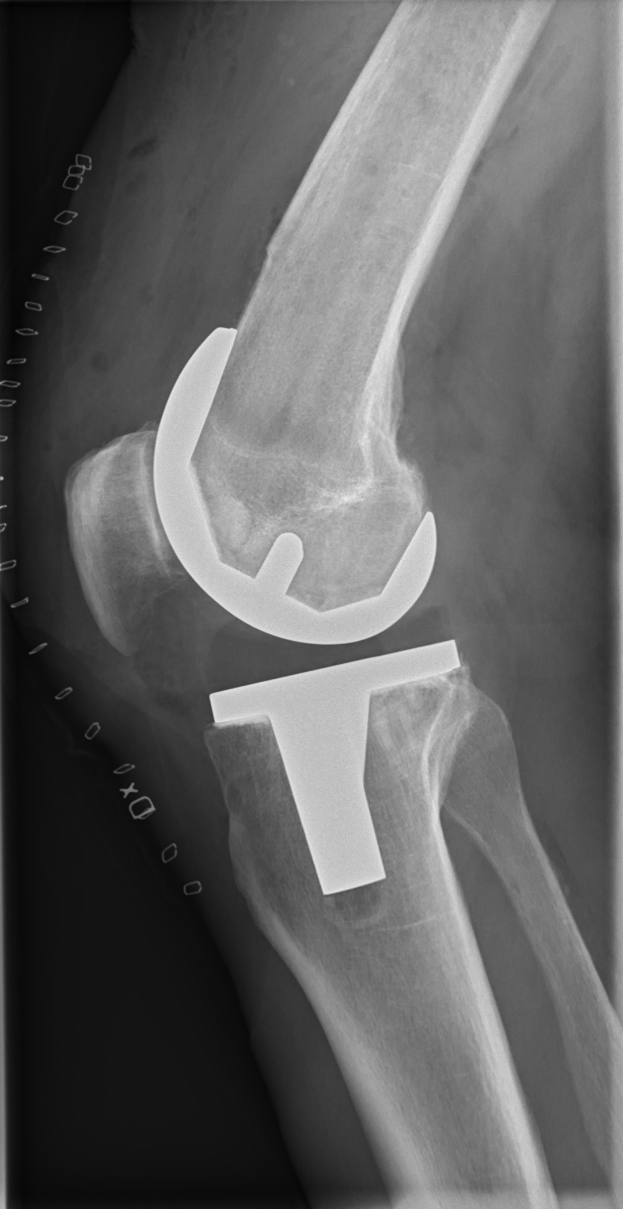

Hack zog sich einen Meniskusriss im rechten Knie zu, der ihn vorerst außer Gefecht setzt. Sein Ausfall verschärft die Probleme der Gladbacher, die in den ersten drei Ligaspielen dieser Saison noch ohne Torerfolg geblieben sind.